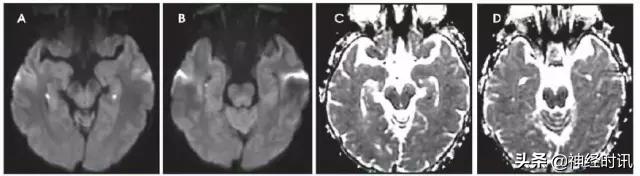

图9 一例53岁女性,酒精性肝硬化,因腹痛、恶心和呕血就诊于急诊。数天后,她出现无反应,伴脑干反射消失,血*水氨**平达360。她被诊断为肝性脑病,MRI显示双侧额叶和岛叶皮层和丘脑轻度弥散受限(A:DWI,B:ADC)和FLAIR高信号(C)。豆状核有轻度T1高信号(D)。

图10 一例48岁女性,精神状态改变、亚急性记忆减退伴步态异常1年,近期出现人格改变。MRI显示双侧基底节、丘脑、皮质弥散受限(A:DWI,B:ADC)和T2-FLAIR(C)高信号。患者被诊断为CJD。

图11 一例43岁男性,发热、头痛、精神状态改变2天,发病2天前曾野营。入院MRI显示双侧基底节、丘脑和岛叶T2-FLAIR(A)高信号和轻度弥散减低(B:DWI,C:ADC),左侧重于右侧。数天后MRI显示更为广泛的基底节和岛叶皮层受累(D:FLAIR)。